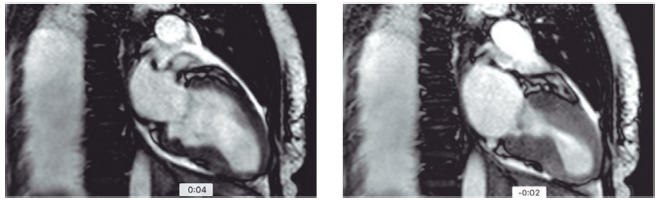

Mulher de 74 anos, obesa, com histórico de depressão, doença renal crônica em estágio III A, chegou ao pronto socorro relatando quadro de dor precordial em opressão e dispneia de início há 30 minutos, após intensa discussão com familiares sobre política. Ao exame físico, apresentou: PA =140x74 mmHg; FC = 100 bpm; ritmo cardíaco regular em dois tempos; bulhas normofonéticas sem sopro; murmúrio vesicular presente sem ruídos adventícios, pulsos presentes e simétricos, sem edema. Foi realizada a cinecoronariografia, devido aos sintomas prolongados e às alterações eletrocardiográficas, que mostrou lesão de 30% em DA e irregularidades em CD; não foi realizada a ventriculografia, a troponina elevou-se acima do percentil 99 e fez curva. Devido à janela ecocardiográfica ruim, foi solicitada a ressonância cardíaca abaixo, que mostrou a diástole (à esquerda) e a sístole (à direita). Ausência de alterações no realce tardio.

Sobre esse caso,